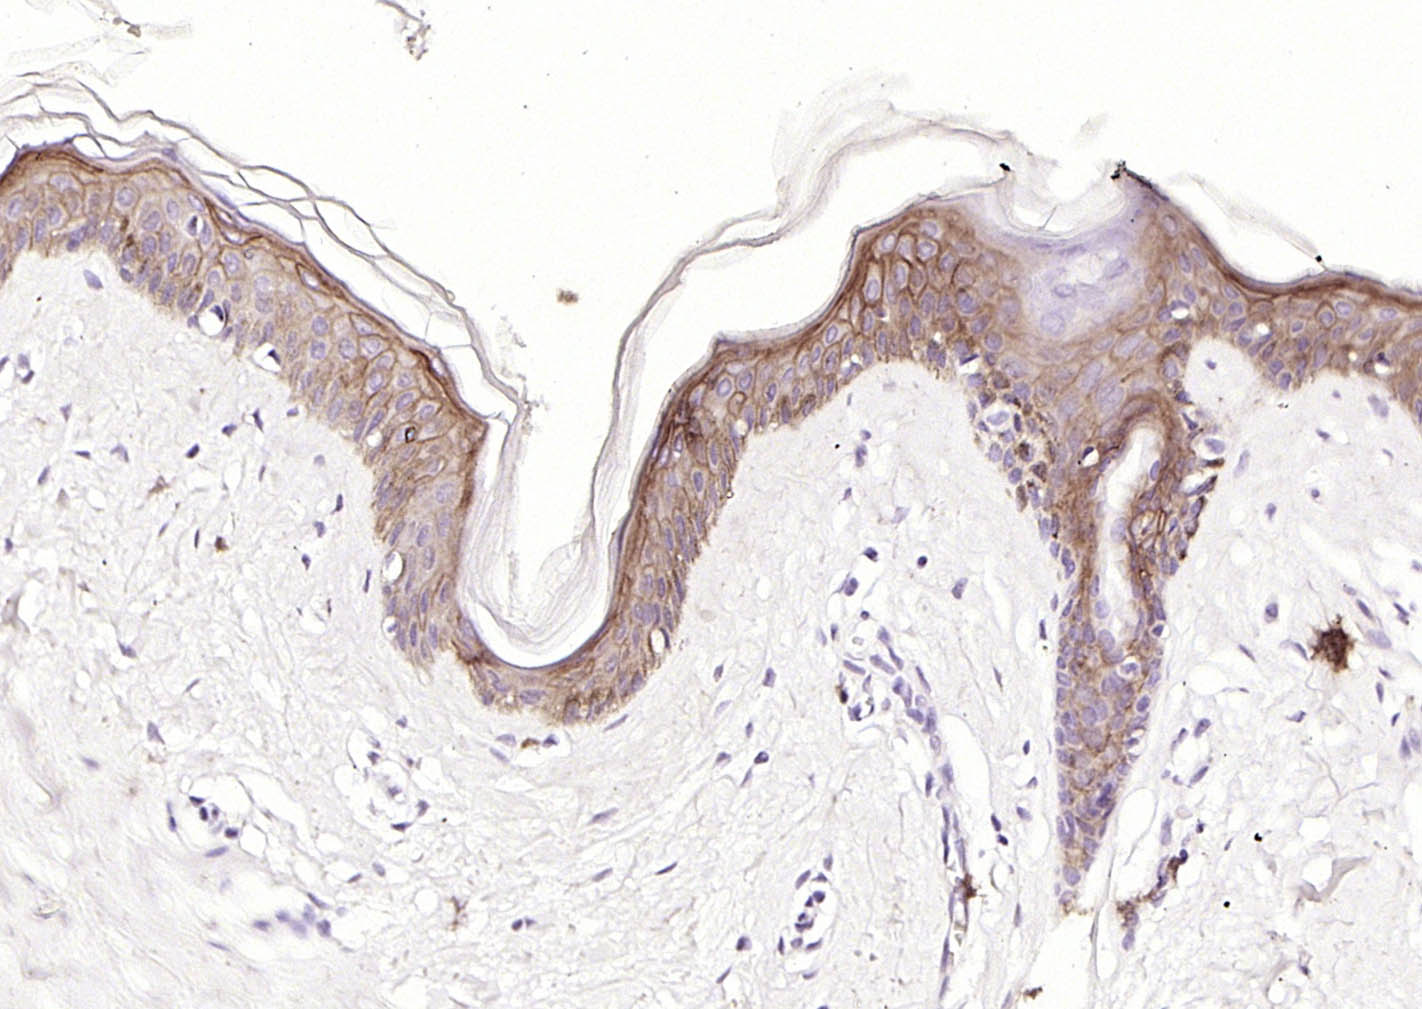

Paraformaldehyde-fixed, paraffin embedded (human Abdominal skin); Antigen retrieval by boiling in sodium citrate buffer (pH6.0) for 15min; Block endogenous peroxidase by 3% hydrogen peroxide for 20 minutes; Blocking buffer (normal goat serum) at 37°C for 30min; Incubation with (CD138) Monoclonal Antibody, Unconjugated (bsm-60902R) at 1:200 overnight at 4°C, followed by operating according to SP Kit(Rabbit) (sp-0023) instructionsand DAB staining.